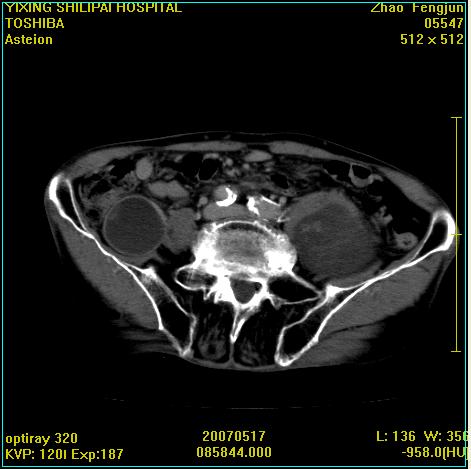

考虑:1、左侧腰大肌囊实性占位性病变(囊性神经根鞘瘤?);

2、右侧兰尾区囊性占位性病变(兰尾囊肿?囊腺癌?类癌?)

以下是引用xiaoniu在2007-5-26 10:45:00的发言:[br]腰大肌的病变应该没有问题,增强扫描还有轻度强化及细小血管影入内,应该排除脓肿,考虑占位性病变,腰大肌的占位多考虑:神经源性肿瘤。另外腹主动脉下端有真假腔的强化,考虑:主动脉夹层。[br][br][本贴已被 xiaoniu 于 2007-5-26 10:46:39 修改过]

以下是引用老爱克斯新网客在2007-5-26 18:26:00的发言:[br]1左下腹囊实性占位肿块,增强后不均匀强化,位于脊柱旁,椎体骨质无破坏软组织无肿胀,考虑神经源肿瘤神经鞘瘤可能大,2右下腹囊性占位性病变,增强后囊壁强化,考虑阑尾囊肿或囊腺瘤,